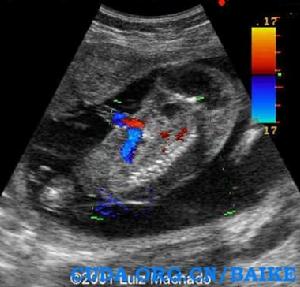

超聲特徵:

· 特徵性表現是都卜勒出現反向動脈灌注。可見臍動脈血流從胎盤朝向無心胎,靜脈血流則反向。這是由於無心胎沒有心臟泵血只能依靠與胎盤的動脈-動脈交通從正常胎兒處竊血。

超聲圖例: